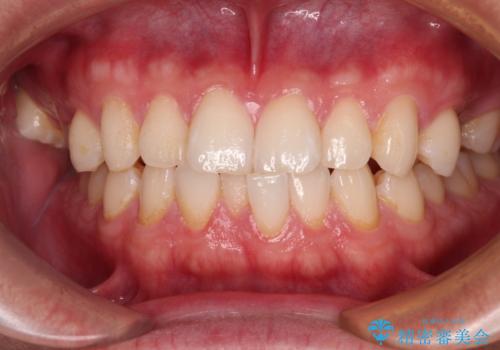

- 上下顎前歯部の非接触(開咬)と下顎のデコボコを主訴に来院された患者様です。

舌のトレーニングは継続して行ってもらっているため、開咬や抜歯したスペースの後戻りはなく、経過は良好です。